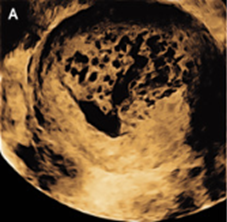

経腟超音波では「吹雪」パターンを形成する多数の嚢胞性スペースを伴う子宮内腫瘤が示された。